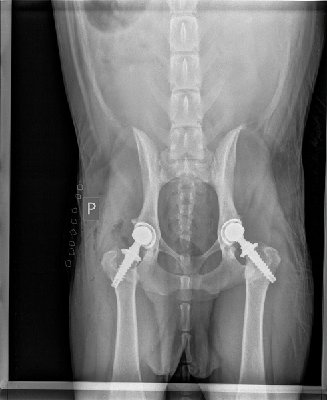

Pierwsza operacja Belli miała miejsce 11 Lipca 2019r, odbyła się w klinice w Czechach u najlepszego specjalisty dr Novaka. Zanim jednak Sunia poddana była operacji to w Maju była oczywiście wcześniej na konsultachach u dr Novaka i wykonane miała niezbędne badania i prześwietlenia w celu przygotowania jej do zabiegu.

Operacja przebiegła pomyślnie i Bella wróciła do Polski, aby tam pod okiem swoich opiekunów spokojnie dochodzić do pełni sił. Na szczęście jak na młode ciałko przystało Bella bez trudu i komplikacji przeszła okres rekonwalescencji i już po paru miesiącach rana była zagojona, a Bella cieszyła się swoją nową protezą. Oczywiście nie mogliśmy polegać jedynie na jej dobrym samopoczuciu, Bella odbyła wizytę kontrolną u dr Novaka, który potwierdził dobre wieści - Endoproteza przyjęła się poprawnie, Bella stawia kroki w prawidłowy sposób, rokowania bardzo dobre.

Wiedzieliśmy, że czeka ją jeszcze druga operacja ale okres Covidowy niestety przesunął termin zabiegu. I tak przyszedł październik 2020r. po wcześniejszych konsultachach i badaniach Bella ponownie została poddana zabiegowi wszczepienia drugiej endoprotezy. Na szczęście i tym razem Sunia świetnie przeszła okres rekonwalescencji i obecnie jest już po kontrolnej wizycie u dr Novaka, który ocenił jej chód na poprawny i tym samym jego opieka nad Bellą dobiegła końca. Dziękujemy Doktorowi za profesjonalną opiekę i wszelkie rady oraz wsparcie, którymi dzielił się z nami przez ostatnie 2 lata.

Poniżej wklejamy uproszczone rozliczenie oraz zdjęcia faktur a także RTG naszej cyber-Belli :)

RTG po 2 operacjach Bella